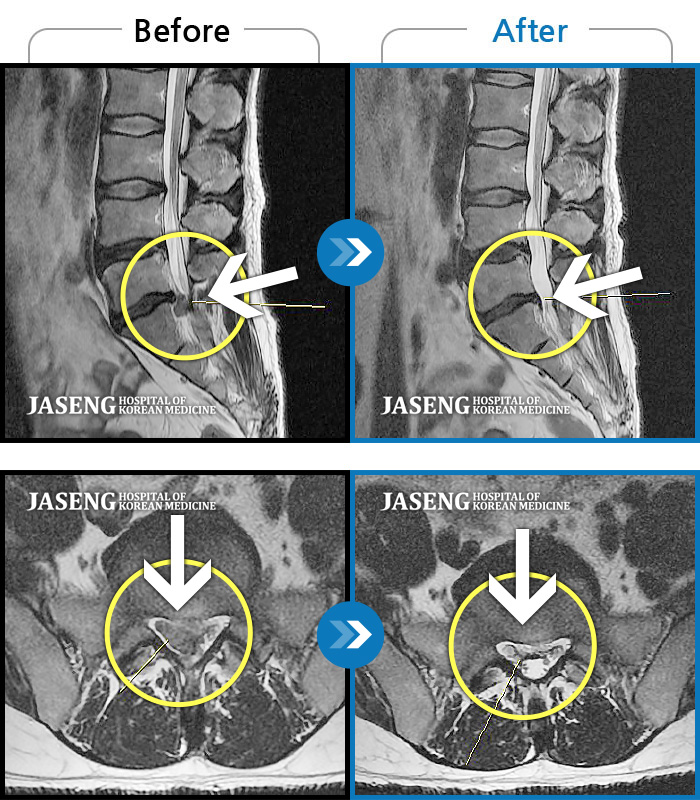

Before

After

환자에게 사전 동의를 받아 동일 조건에서 촬영되었습니다.

개인에 따라 치료 후 부작용이 발생할 수 있으니 의료진과 상담 후 치료를 진행하시기 바랍니다.

양측 허리부터 양측 골반 통증, 좌측 허벅지부터 종아리 후면부 통증 및 저린감

일상생활이 힘들 정도의 허리 통증과 왼쪽 다리 통증